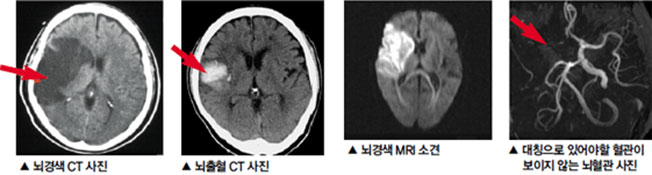

뇌경색은 뇌의 혈관이 막혀서 뇌에 산소와 영양분이 공급되지 않게 되는 상태를 의미합니다. 이런 혈액 공급이 차단되면 뇌세포가 손상되거나 사멸하게 됩니다. 급성 뇌경색은 시간이 지남에 따라 위험성이 증가하므로, 초기 증상을 빠르게 인식하는 것이 필요합니다. 뇌경색은 주로 고혈압, 고지혈증, 당뇨병 등의 만성 질환과 연관이 있습니다.